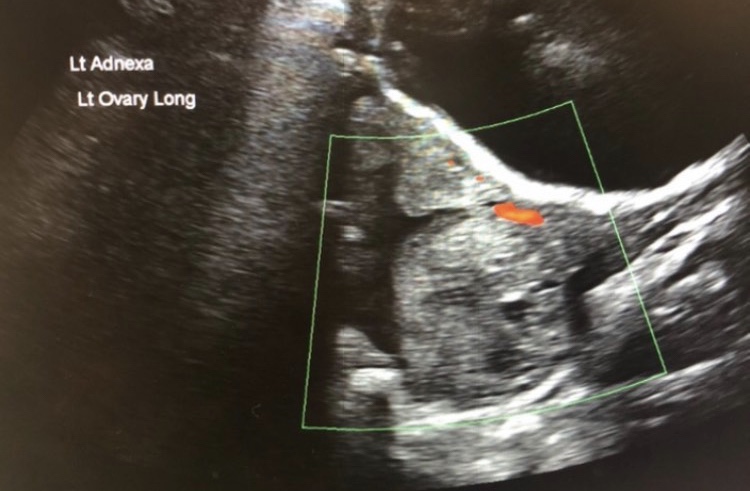

Sonographic findings

- Unilaterally enlarged ovary

- Peripherally displaced follicles due to edema

- Coexistent mass

- Twisted pedicle (not always seen)

- Free fluid

Doppler

- little or no intra-ovarian venous flow

Left ovarian torsion with laparoscopic image